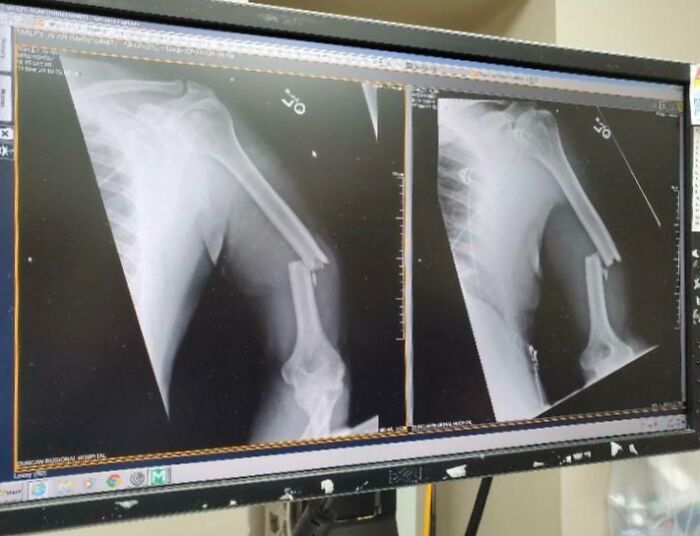

#58 11 Years Ago, My Mom Had Pins Surgically Placed In Her Knee. Today, The Pins Are Nearly Protruding Her Skin

Image credits: unidentifies